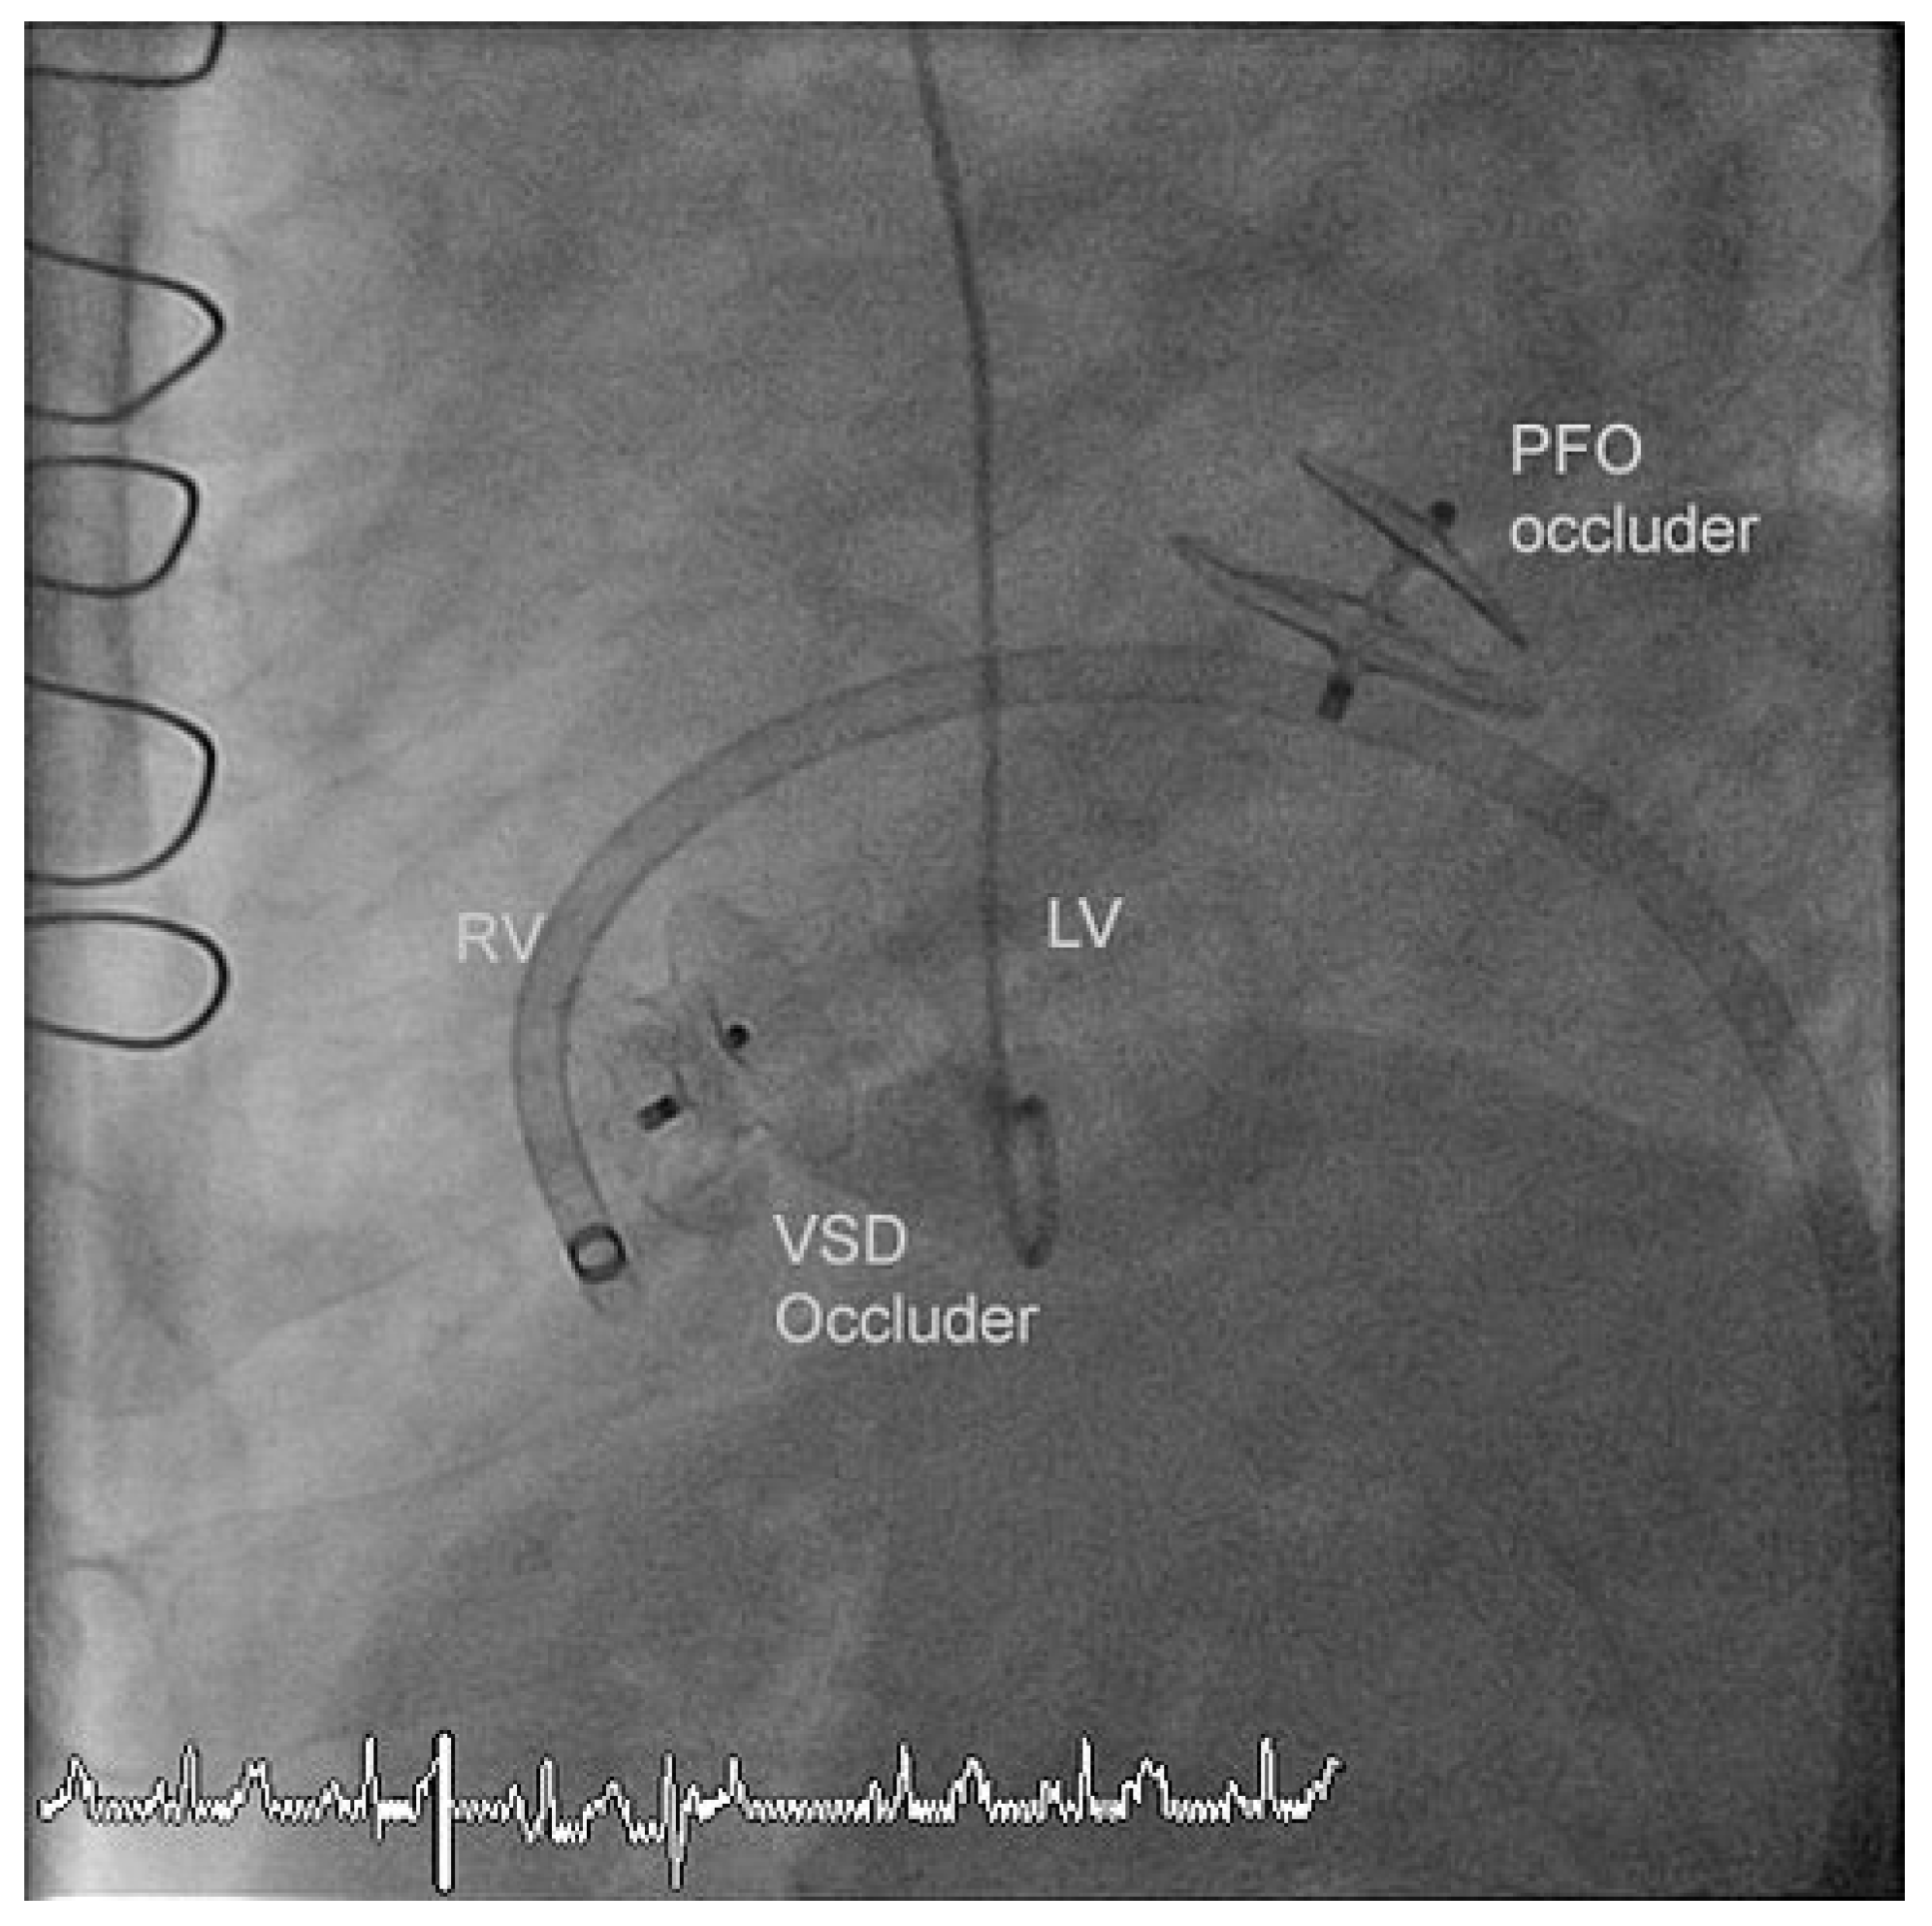

The residual VSD was identified with left ventricular contrast injection and the defect was crossed from the left ventricular side using a guide wire which was snared in the pulmonary artery and exteriorized thus creating an arteriovenous loop. The VSD was measured using a 34 mm sizing balloon (St. Jude-AGA) (Figure 1). A 14 mm Amplatzer muscular VSD occluder (St. Jude-AGA) was implanted through an 8 F TorqVue sheath (St. Jude-AGA) inserted through the right femoral vein (Figure 2). Adequate position was confirmed under fluoroscopy with contrast injection into the left ventricle (Figure 3). The procedure was performed without TEE and under local anaesthesia.

At the same time coronary angiography detected a total (re-)occlusion of the posterior descending and the posterolateral branch of the right coronary artery and a significant stenosis of the distal right coronary artery which were treated with balloon angioplasty. The PFO Amplatzer Occluder implanted seven years earlier was free of residual shunt.

Figure 3. Adequate position of the VSD occluder with minimal residual shunt in the old PFO Occluder.